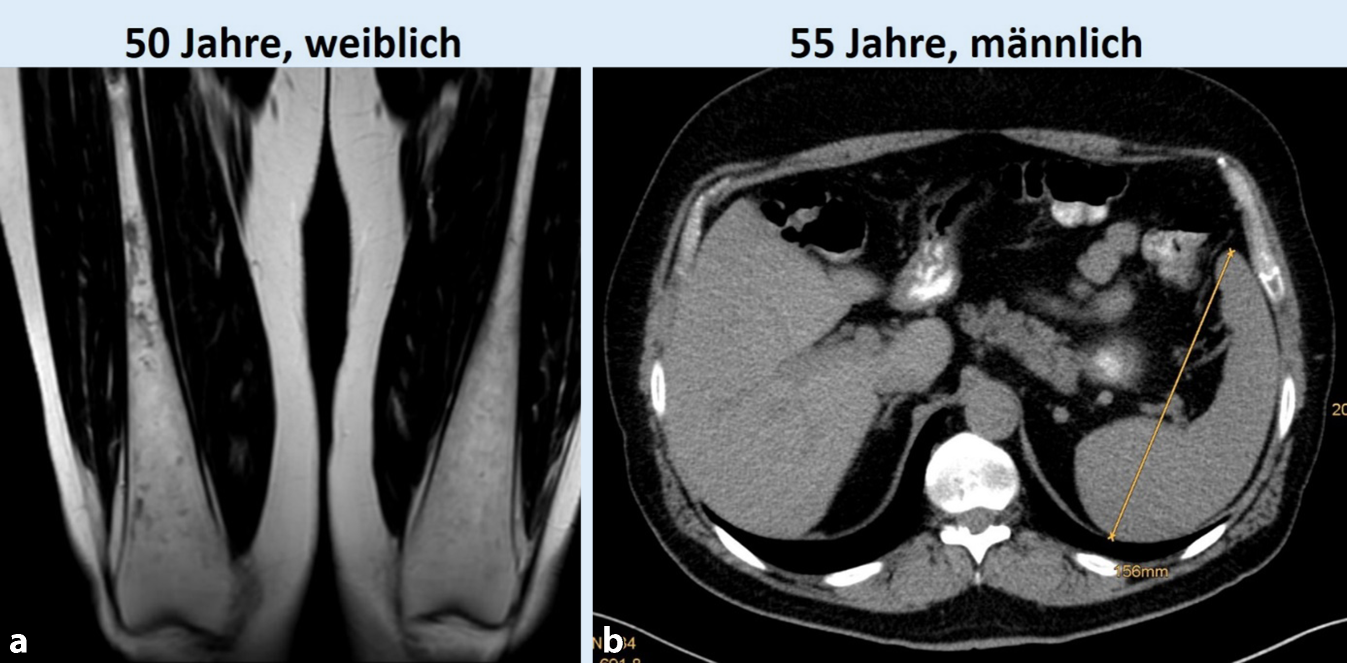

Abb. 2

Knochenmarkbeteiligung bei Morbus Gaucher bei einer 50-jährigen Patientin (a) und milde Splenomegalie (15,6 cm,) bei einem 55-jährigen Patienten (b). Dargestellt ist die typische Auftreibung der Diaphysen der Femora im Sinne der sog. Erlenmeyer-Kolben-Deformität, die analog zur Entstehung der Hepatosplenomegalie auf der Speicherung von Glukosylceramid in Makrophagen beruht

Das führende Symptom ist die ausgeprägte Fettleber mit Hepatomegalie, nur in geringerem Ausmaß erfolgt die lysosomale Speicherung in Makrophagen, was eine moderate Splenomegalie bedingt. Histologisch ist in der Leberbiopsie die panlobuläre mikrovesikuläre Steatose ein wichtiger hinweisender Befund (Abb. 3). Eine mikrovesikuläre Steatose sollte immer an eine genetisch-metabolische Ursache und damit auch eine LAL‑D denken lassen, wenn eine medikamentös-toxische Schädigung (z. B. Antiepileptika, Antidepressiva via mitochondriale Toxizität) ausgeschlossen wurde.

Abb. 3

Befund eines 26-jährigen beschwerdefreien Patienten mit Hepatosplenomegalie mit lysosomaler saurer Lipase-Defizienz (LAL-D). a MRT. b zeigt den Befund der Leberbiopsie mit dem Lysosomenmarker Cathepsin D, der die generalisierte lysosomale Speicherung von Cholesterinestern und Triglyzeriden zur Darstellung bringt